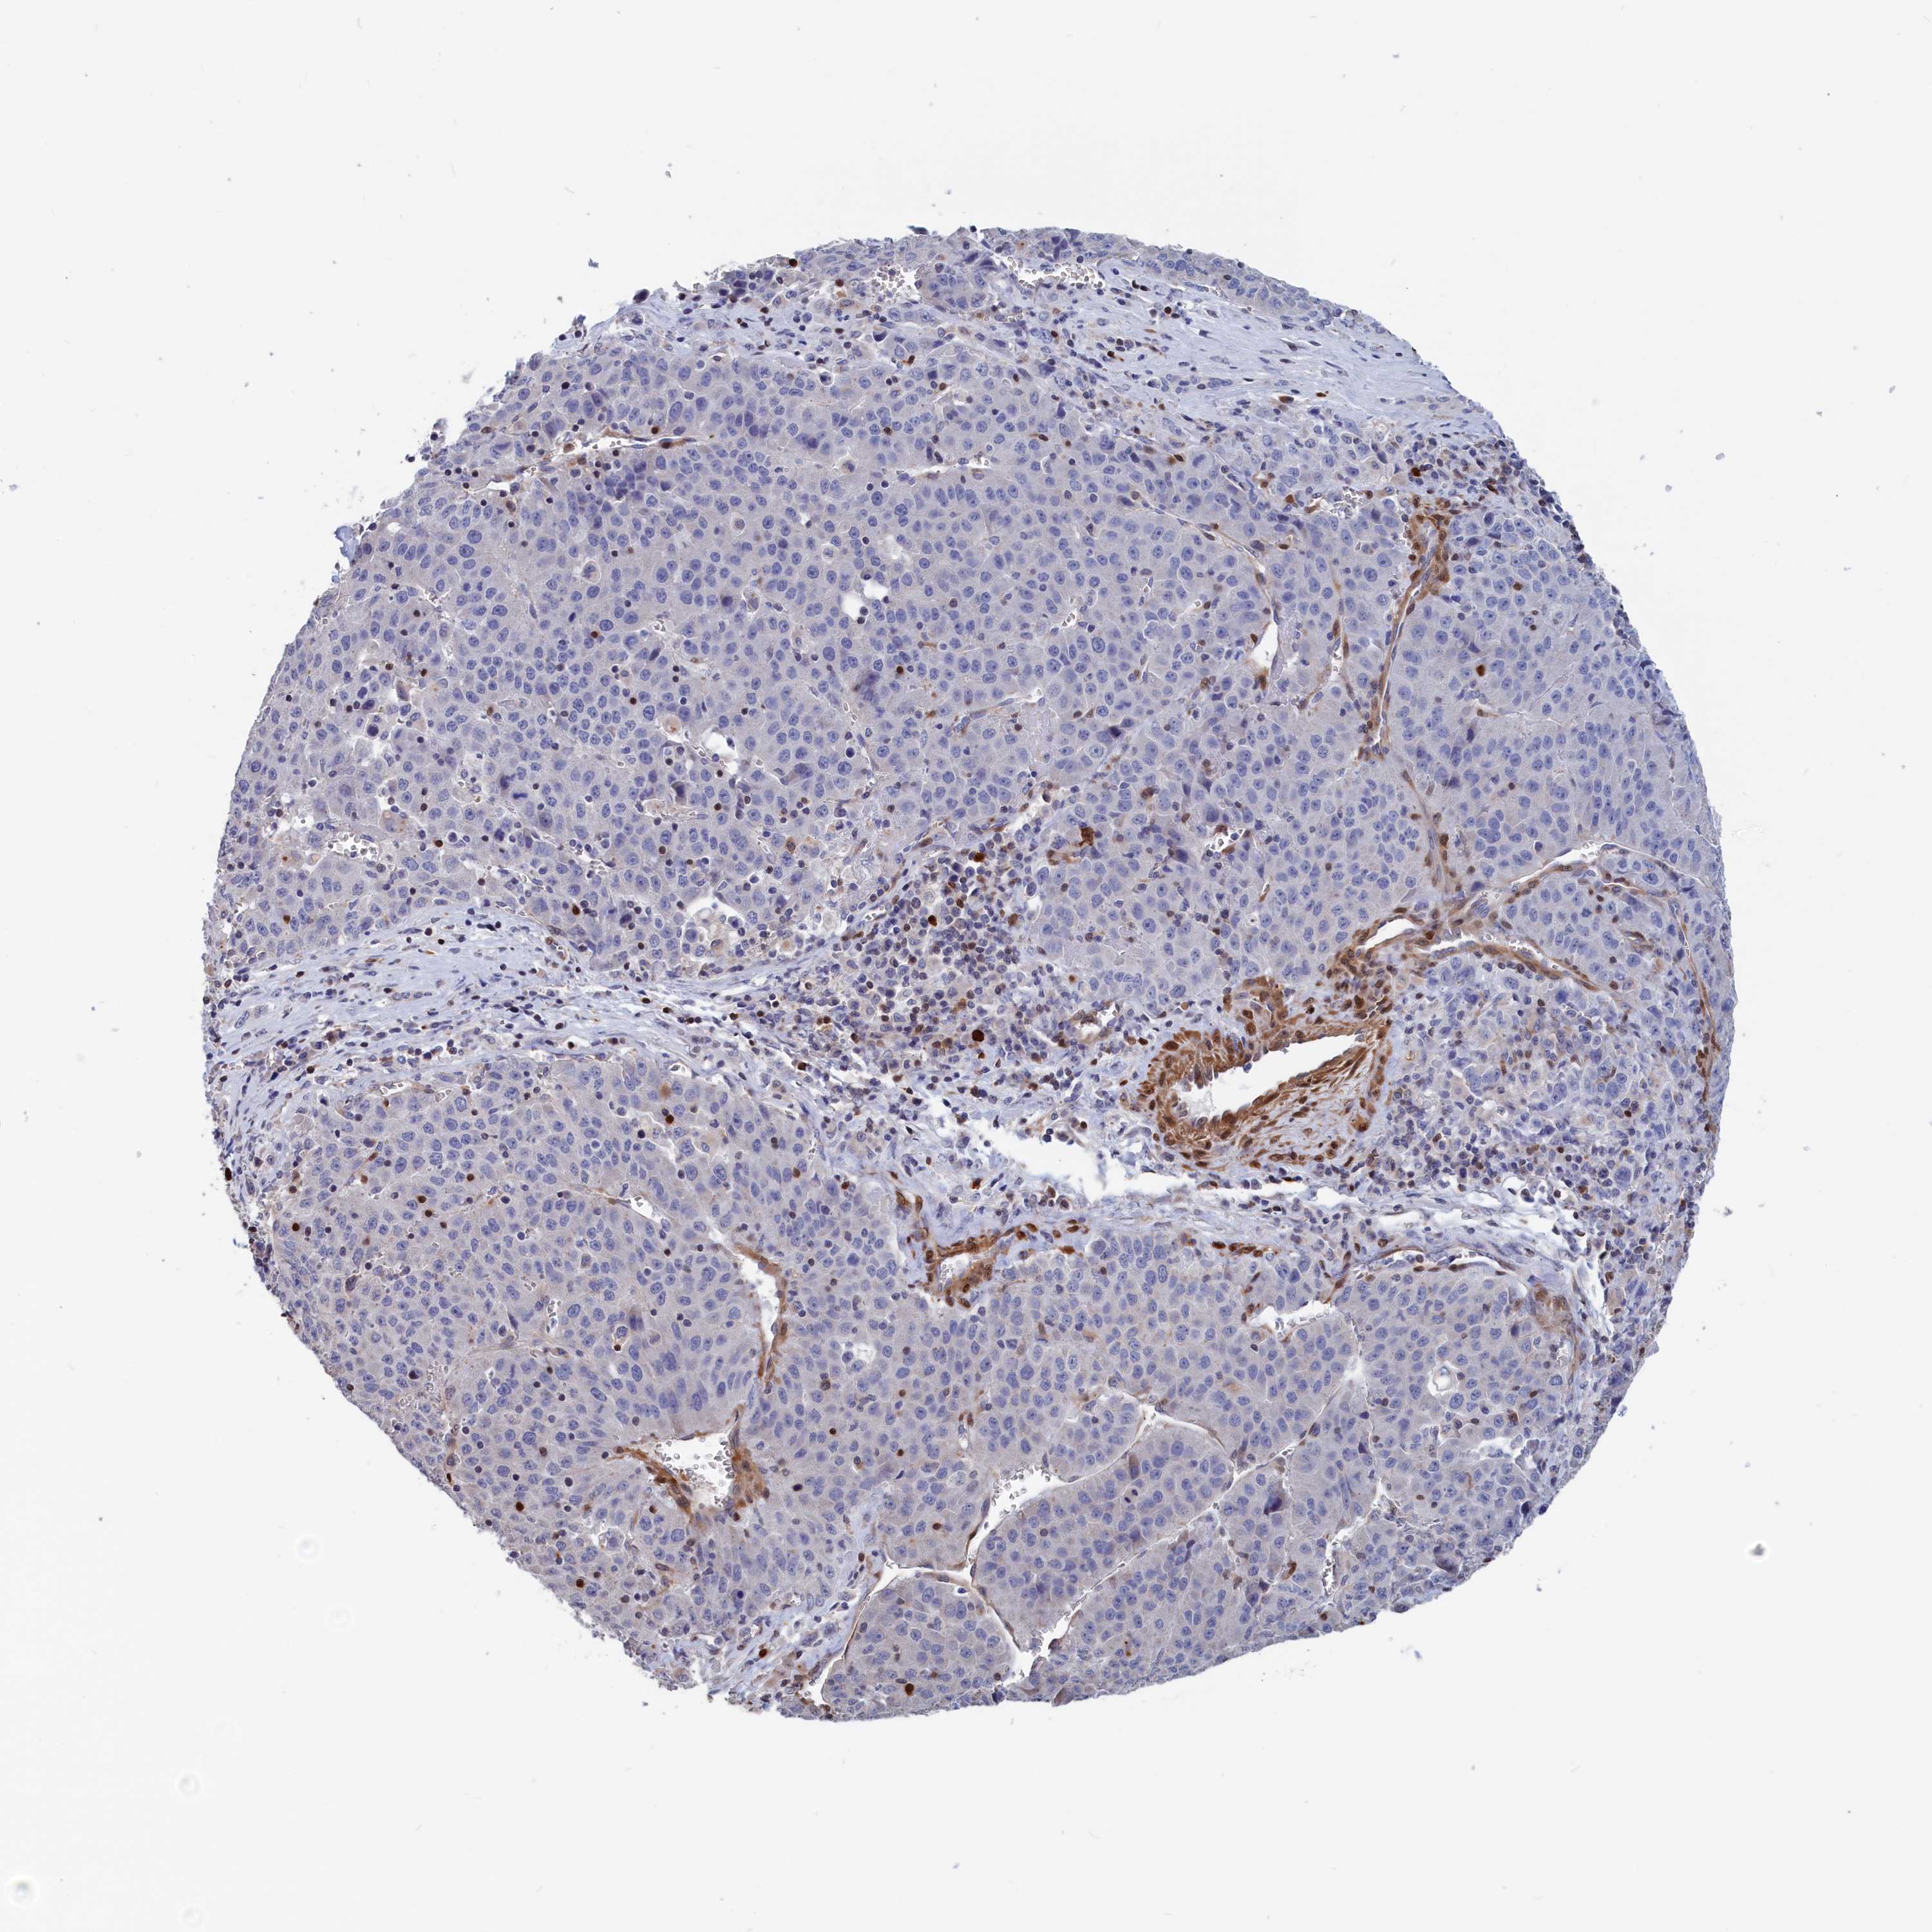

LIVER CANCER - Protein expressioni

A mouse-over function shows sample information and annotation data. Click on an image to view it in a full screen mode. Samples can be filtered based on level of antibody staining by selecting one or several of the following categories: high, medium, low and not detected. The assay and annotation is described here.

Antibody stainingi

Antibody staining in the annotated cell types in the current human tissue is reported as not detected, low, medium, or high, based on conventional immunohistochemistry profiling in selected tissues. This score is based on the combination of the staining intensity and fraction of stained cells.

Each image is clickable and will lead to virtual microscopy that enables deeper exploration of all samples and also displays staining intensity scores, fraction scores and subcellular localization as well as patient and tissue information for each sample.

Antibody HPA042462

Staining

High

Medium

Low

Not detected

Intensity

Strong

Moderate

Weak

Negative

Quantity

>75%

75%-25%

<25%

None

Location

Nuclear

Cytoplasmic/membranous

Cytoplasmic/membranous,nuclear

Cholangiocarcinoma

Carcinoma, Hepatocellular, NOS